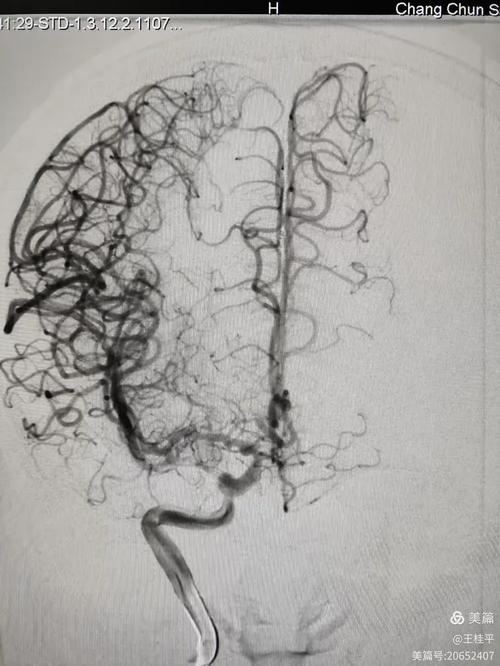

诊断病因:寻找脑梗的“元凶”

脑梗的直接原因是脑部血管被堵住了,TCD可以帮助医生判断这个“堵点”在哪里,以及堵塞的原因是什么。

发现血管严重狭窄或闭塞:

- 血流速度显著增快: 这是最典型的表现,当血管因为动脉粥样硬化等原因变窄时,就像河道变窄河水流得更快一样,血流速度会急剧升高,TCD可以非常敏感地捕捉到这种变化,提示医生可能存在严重狭窄。

- 血流信号消失: 如果一条血管完全堵死了,TCD可能就探测不到该血管的血流信号,提示血管闭塞。